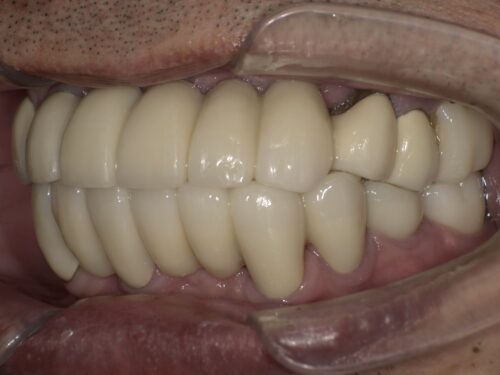

治療後の写真です。

前歯はブリッジとよばれる治療法で治しました。

根元の歯ぐきは赤みがなくなり健全な状態になりました。

奥歯でもしっかり噛めるようにすることで前歯にかかる負担を軽減しています。

前歯の傾きも改善して、上下の前歯が本来の位置関係で噛めています。

ただ、歯周病の影響で歯ぐきが下がっており、そこのブラッシングはしっかり続けていく必要があります。

歯一本一本だとグラグラしてしまうような状態でも、

ブリッジといってかぶせ物でつなぐことで全体として強度が上がるようにしています。

下の奥歯はインプラントを入れることで噛める範囲を増やしています。